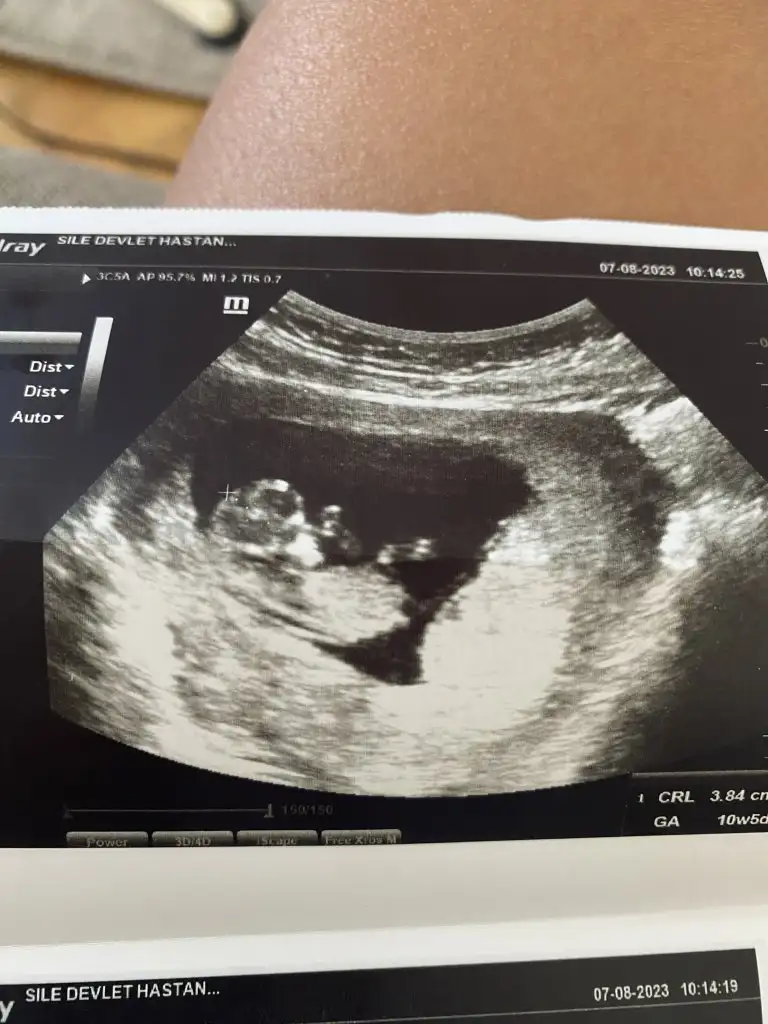

İlk iki resim ilk ultrason sonrakiler de en son ultrason bende tahmin alabilirmiyim